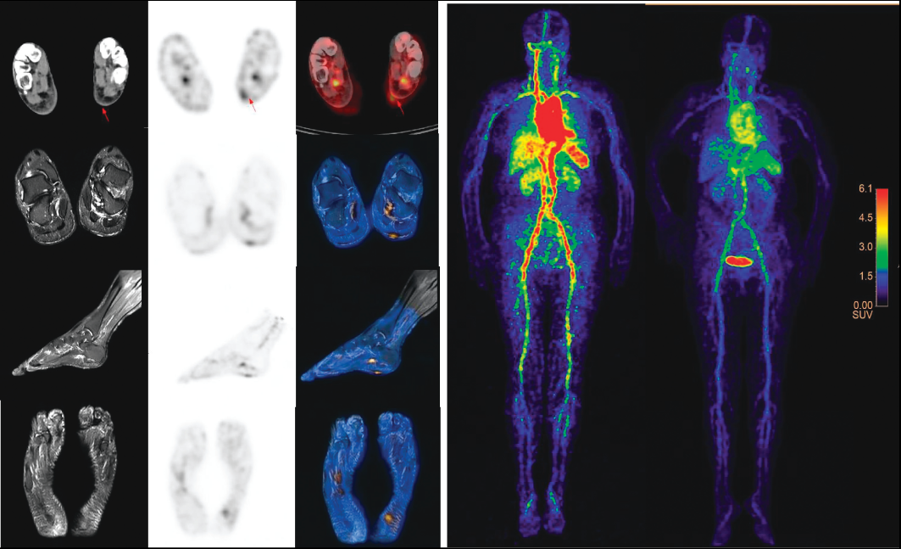

4. 针对肿瘤免疫治疗(抗PD-1治疗)优势患者筛选及疗效评价挑战,研制出新型固体靶核素124I,优化出室温条件60秒快速、原位标记单抗技术,实现基于我国NMPA批准的首个抗PD1治疗药物(JS001, 特瑞普利单抗)的直接放射性标记的临床研究。相关成果以Positron Emission Tomography Imaging of Programmed Death 1 Expression in Cancer Patients Using 124I-Labeled Toripalimab:A Pilot Clinical Translation Study为题,于2021年5 月发表在Clinical Nuclear Medicine 杂志上。

图4: I-124标记PD1单抗的PET 临床转化